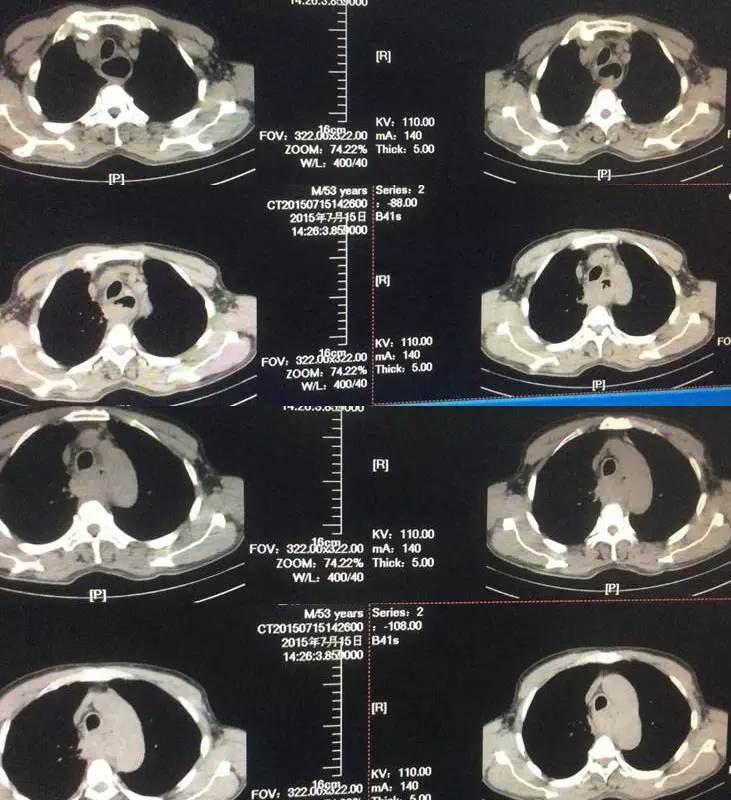

胸部CT:双肺出现多发高密度结节。

4、肺转移:从CT来看双肺多发小结节,考虑转移可能,建议对比既往CT,一方面是评估原来是否有病灶,另一方面评估转移灶倍增时间,即转移肿瘤的生长速度。